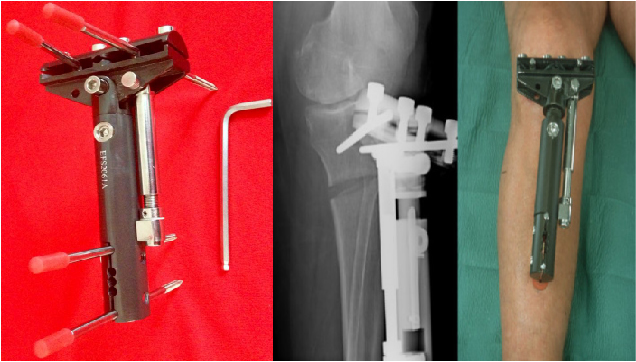

MATERIAL: FIBRA DE CARBÓN Y ACERO

COMPONENTES:

- FIJADOR HTO

- Tornillo Schanz rosca de 5,5 mm

- Llave hexagonal 6 mm

INDICACIONES:

- Alargamiento

- Corrección de Deformidad Con Aumento

- Osteotomías de tibia proximal para Corrección de la Deformidad de Varo y Valgo.